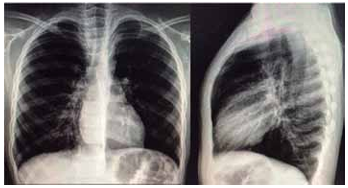

Paciente de 8 anos com asma mal controlada e trazido para avaliação em pronto-atendimento por sintomas de tosse seca e desconforto respiratório há um dia. À admissão, encontra-se em regular estado geral, taquidispneico, com FR = 48 ipm, SatO2 = 86% em ar ambiente; presença de tiragens intercostal e de fúrcula e ausculta pulmonar com sibilos inspiratórios e expiratórios, com tempo expiratório prolongado. Não há prejuízo do nível de consciência. Realizadas três inalações com salbutamol e ipratrópio nas doses adequadas, além de corticoide sistêmico; mantido em máscara não reinalante.

Após todas essas medidas, paciente segue com desconforto respiratório, FR = 44 ipm, SatO2 = 94% em máscara; ausculta pulmonar com o mesmo padrão inicial. Realizada radiografia de tórax a seguir.

(Arquivo pessoal; imagem usada com autorização)

Qual das alternativas a seguir contém a conduta mais adequada a ser realizada no momento?